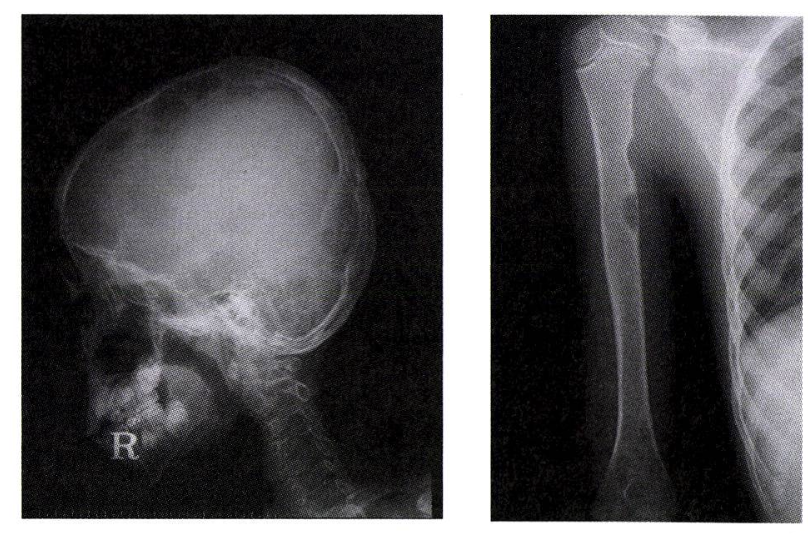

뼈: 가장 흔함(80%). 두개골, 장골 등에서 통증, 부종, 병적 골절을 유발하는 용해성 병변.

뼈 엑스선사진: punched out defect, 지도모양의 병소, 편평 척추, 장골 골절 등